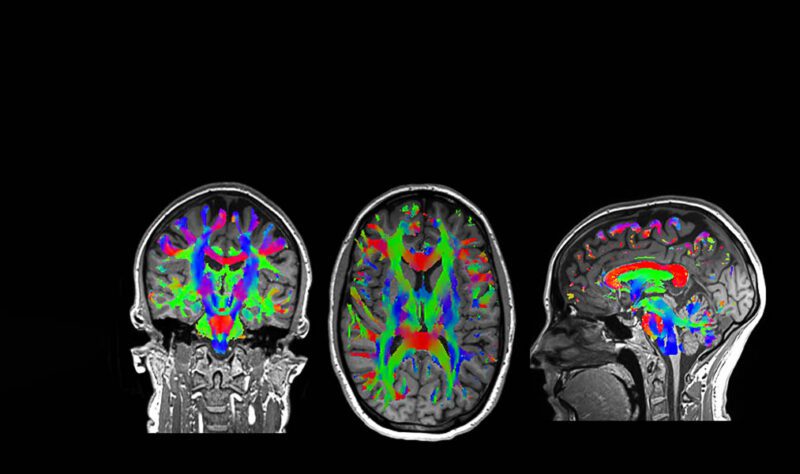

MRIs image soft tissue structures in the body – for instance, the brain, eyes, heart and ligaments around joints such as shoulders.

The new Bio Matrix capability of this scanner uses artificial intelligence (AI), which auto-detects motion and results in some fantastically clear images.

“It can scan a bigger range and has sensors which help image clarity in the case of patient movement and respiration. Scan times are also quicker on this machine,” Stephen says.

The new generation of MRI scanners produces much better soft tissue contrast in shorter scan times and is being used to scan the abdomen and pelvis with exquisite detail.

Gareth Leeper, charge MRI technologist at Pacific Radiology, says, “The new scanner at Forté is producing the best pictures we have ever seen of the nerves right down to the hands and feet, and we have seen an increase in the number of referrals for imaging of the leg and arm nerves in patients with chronic pain syndrome.”